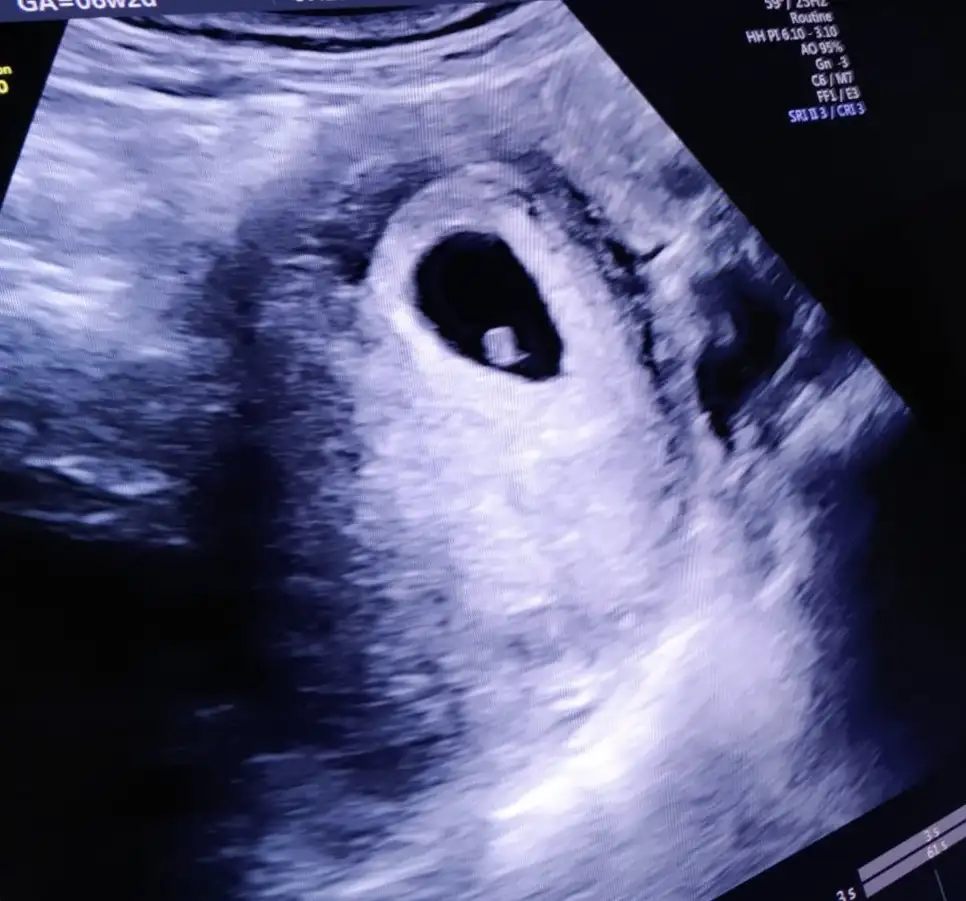

Bu da benim fındık, karından ultrasonla çekildi. Teoriye göre kız görünüyor değil mi😊

İlki 8+4 ,ikincisi 6+6